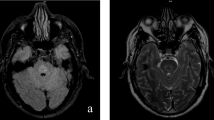

All lesions identified in CNS tissues examined from the 6 CPM patients exhibited active demyelination (Figure 1a, e, i; Figure 2g, h; Figure 3c). Lesions affected the base of the central pons symmetrically (Figure 1a, e, i; Figure 2a; Figure 3a). There was relative preservation of axons and neurons (Figure 2l, m) and, to some extent, of myelin (Figure 1e, i; Figure 2c, g, h; Figure 3c). All lesions were heavily infiltrated by activated macrophages (Figure 2a, b; Figure 3a, b) containing abundant myelin degradation products, a hallmark of active demyelination (Figure 2g, h; Figure 3c). There was a mild degree of T lymphocyte infiltration around vessels and in the parenchyma (Figure 2n; Figure 3o), and evidence of axonal swelling (Figure 2l) and oligodendrocyte apoptosis (Figure 2o). No deposits of complement activation products were found.

AQP1, AQP4 and GFAP protein expression in human CPM lesions. ( a-d ) A demyelinated lesion in the central basis pontis ( a ) of a 56-year-old man with CPM in context of rapidly corrected hyponatremia shows loss of astrocytic AQP4 extending beyond the area of demyelination ( b ), loss of AQP1 ( c ), but retained GFAP ( d ); ( e-h ) A CPM lesion in the central basis pontis of a 53-year-old man with CPM and severe dehydration, malnutrition and hypernatremia shows relative preservation of myelin ( e ), loss of astrocytic AQP4 ( f ), AQP1 ( g ), but preserved GFAP ( h ); ( i-l ) A demyelinated lesion in the central basis pontis ( i ) of a 24-year-old woman with CPM in the context of hepatic failure and hypokalemia shows increased AQP4 ( j ), AQP1 ( k ) and GFAP expression ( l ); ( a, e, i ) PLP; ( b,f, j ) AQP4; ( c, g, k ) AQP1; ( d, h, l ) GFAP; (scale bar = 5 mm).